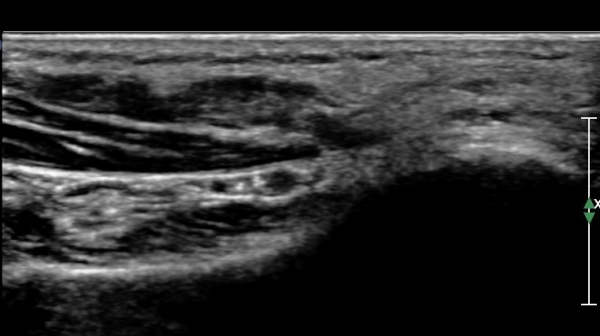

ÃÊÀ½ÆÄ°Ë»ç :  ¹ßµÚ²Þ ³»Ãø¿¡¼­ ¾Æ·¡µÚ²ÞÄ¡½Å°æ(inferior calcaneal nerve : Baxter's nerve) Ⱦ´Ü¸é °Ë»ç»ó

¹«Áö¿ÜÀü±Ù°ú Á·Àú¹æÇü±Ù(quadratus plantae) »çÀÌ¿¡¼­ ¾Æ·¡ µÚ²ÞÄ¡µ¿¸Æ ÈĹ濡 ¾Æ·¡µÚ²ÞÄ¡½Å°æÀÌ

Àú¿¡ÄÚ ¸ð¾çÀ¸·Î °üÂûµÈ´Ù(»çÁø 1, 2).